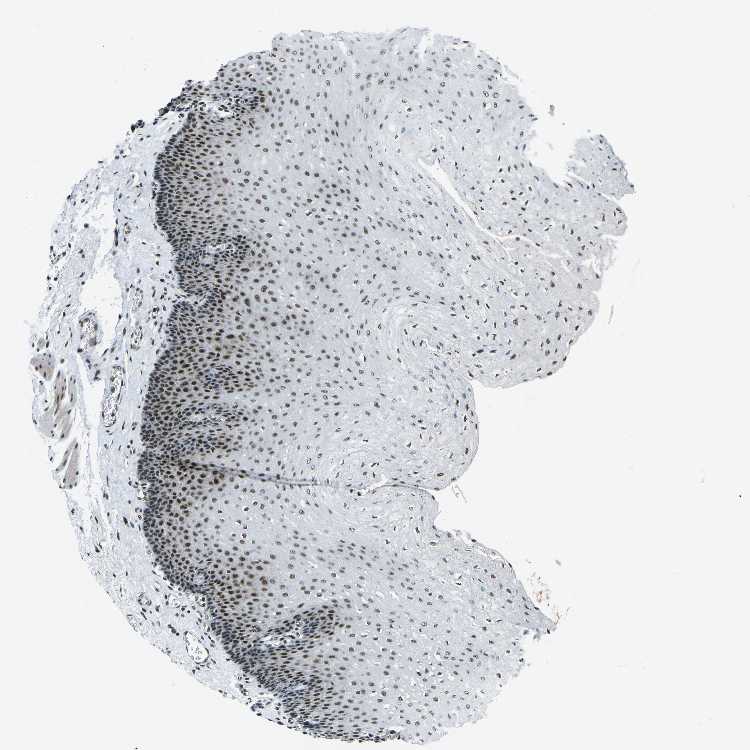

TISSUE PRIMARY DATA ESOPHAGUS Show tissue menu

Esophagus

ESOPHAGUS - Antibody stainingi

Antibody staining in the annotated cell types in the current human tissue is reported as not detected, low, medium, or high, based on conventional immunohistochemistry profiling in selected tissues. This score is based on the combination of the staining intensity and fraction of stained cells.

Each image is clickable and will lead to virtual microscopy that enables deeper exploration of all samples and also displays staining intensity scores, fraction scores and subcellular localization as well as patient and tissue information for each sample.

Antibody HPA019703Antibody CAB016547

Squamous epithelial cells HighHigh